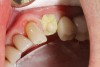

A 71-year-old man presented with acute pain in tooth No. 29 that was spontaneous, unresponsive to vitality testing, and sensitive to percussion. He was referred to an endodontist for treatment of acute apical periodontitis due to the non-vitality of the nerve. Because of the multiple restorations and lingual decay of the tooth, enamel and dentin were compromised, causing the tooth to be biomechanically at high risk and requiring an eventual post-and-core and crown (Figure 1 and Figure 2). Endodontic care included nonsurgical intracanal therapy and creating room for a post space.

Fig 1. Multiple restorations decrease enamel and dentin strength, requiring full-coverage enhancement.

Figure 1

Fig 2. Preoperative view of tooth to be restored shows defective Class 5 restoration that unfortunately was mirrored on the lingual gingival margin.

Figure 2